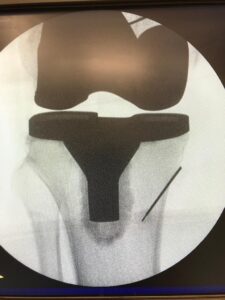

L’infiltrazione permette attraverso l’iniezione di farmaci con con attività antinfiammatoria e/o lubrificante di trattare la patologia dolorosa in relazione a spalla, ginocchio, anca e piccole articolazioni;

Utile nei pazienti affetti da dolore articolare di natura artrosica o reumatica che non rispondono alle terapie conservative (farmaci e/o fisioterapia), ed in cui è necessario ridurre l’infiammazione o nutrire la cartilagine e la sinovia. L’infiltrazione, effettuata sotto guida ecografica per una visualizzazione precisa del target, consiste nell’iniezione di farmaci (con attività antinfiammatoria e/o lubrificante) all’interno delle articolazioni (anca, ginocchio, spalla, faccette articolari lombari e cervicali, piccole articolazioni della mano e del piede), allo scopo di ridurre la sintomatologia dolorosa.